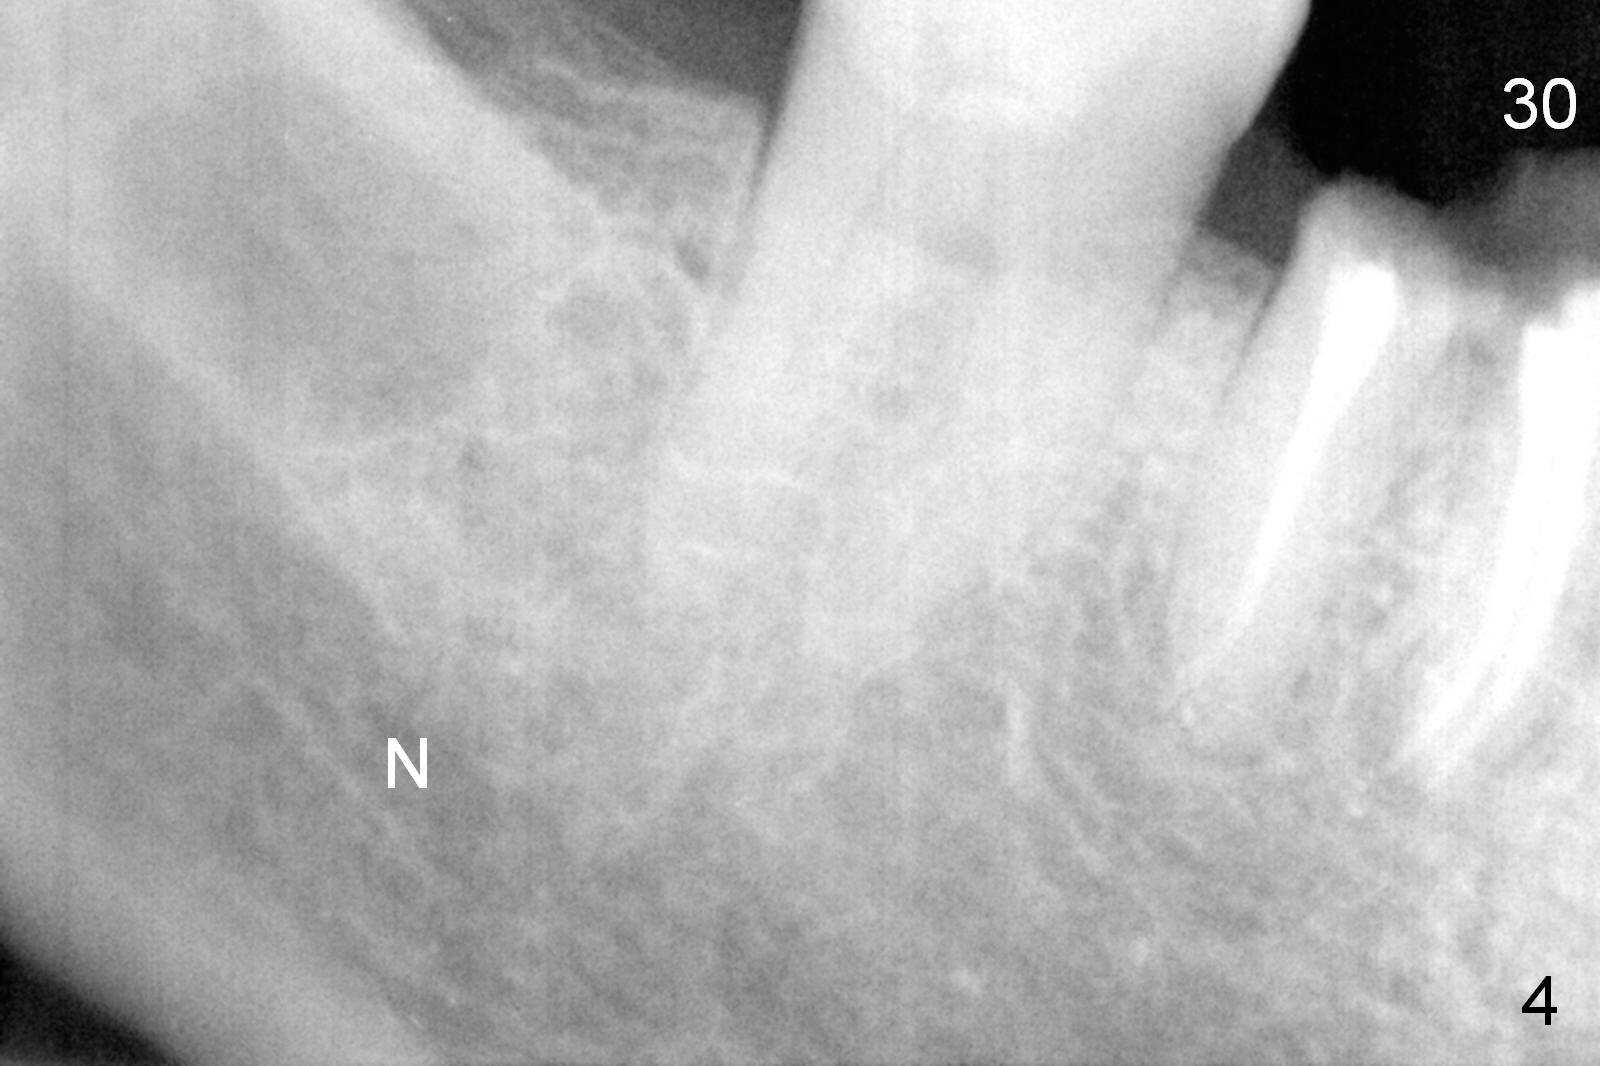

A 68-year-old lady (WQ) had CT taken 3 years ago (Fig.1-3), which show 3 roots (M: mesial; DB: distobuccal; DL: distolingual) of the lower right 1st molar and large caries (C).  Recently the tooth fractures after root canal therapy (Fig.4-6).